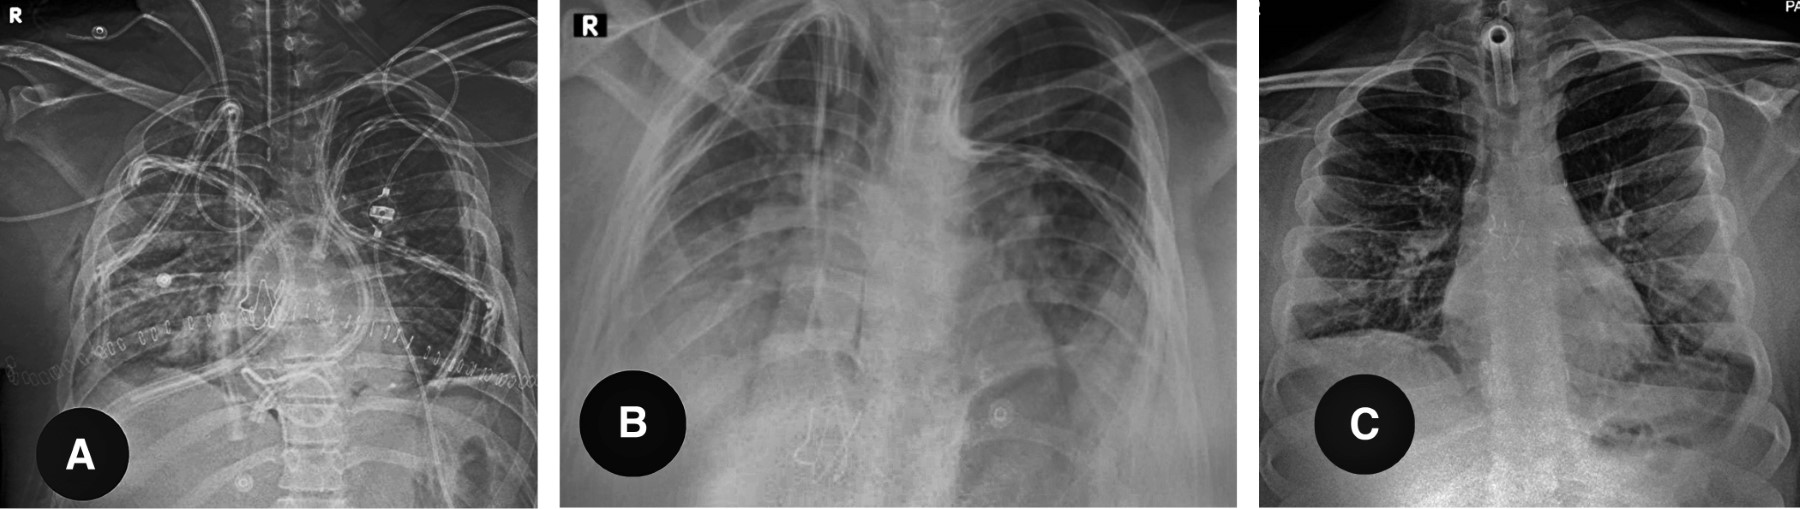

Bajo consentimiento informado y aprobación por los comités de ética y trasplante hospitalarios, con paciente en posición de supino modificada por un bulto transversal torácico, anestesia general, intubación selectiva y monitoreo anestésico para procedimiento cardiovascular mayor, 3 además de Swan-Ganz, ecocardiograma transesofágico, neuromonitoreo y línea arterial, se colocaron introductores arteriales y venosos femorales derechos, se realizó incisión de Clamshell y se procedió a disección del hilio pulmonar, se administraron 5,000 UI de heparina y 500 mg de metilprednisolona, se realizó prueba de pinzado de arteria pulmonar con pinza Satinsky por cinco minutos, sin evidenciar incremento de la presión de arteria pulmonar, inestabilidad hemodinámica o ventilatoria, se colocó una rienda de poliéster del 5 al domo del diafragma para tracción por contraabertura. En la neumonectomía derecha, se cortó arteria, vena y bronquios con cartuchos de 45 mm de engrapadora endocavitaria con grapas de 2.5 mm a vasos y 3.8 a bronquios. Se confeccionó muñón bronquial de receptor preservando tejido peribronquial y cauterizando lo menos posible el borde libre. Se procedió a introducir injerto inflado para verificar que el exceso de tamaño no fuera muy importante, se improvisó una chaqueta enfriadora con una compresa empapada de solución salina fría y se procedió a anastomosis bronquial con poliglactina 910 recubierta 4-0 CT1 en surgete a porción membranosa y puntos separados en cara anterior, reforzando con tejido ganglionar la línea de sutura, se verificó integridad y simetría de la misma con broncoscopia, posteriormente se anastomosó arteria pulmonar con polipropileno vascular 5-0 aguja RB-1 en surgete continuo con técnica de paracaídas, se purgó aire antes del cierre; finalmente aurícula con surgete continuo igualmente con polipropileno vascular 4-0 aguja RB1, reperfusión controlada con 25 hasta 50% de flujo por tres minutos, se purgó el aire por anastomosis auricular y se verificó permeabilidad sin turbulencia con ecocardiografía transoperatoria. Se realizó hemostasia meticulosa y se colocaron dos sondas pleurales de silicona 24FR conectadas a sello de agua y succión -20 cc. Posteriormente, se procedió a neumonectomía e implante izquierdo en la misma secuencia (Figura 2). En este lado al revisar la anastomosis bronquial se observó asimetría con protrusión de tejido en la luz, por lo que se rehízo la anastomosis con puntos separados del mismo material observando adecuada simetría y permeabilidad, la reperfusión se efectuó en la misma forma, se colocaron dos drenajes pleurales, se retiraron suturas de tracción a diafragma bilaterales. Se procedió a cierre de incisión, se cambió tubo selectivo por uno convencional y se inició la ventilación mecánica de protección. Se trasladó paciente a unidad de cuidados intensivos con soporte vasopresor mínimo, sedación y parámetros de ventilación de protección (Figura 3).

EVOLUCIÓN

Se extubó a las 48 horas postquirúrgicas. Luego, a las 48 horas, presentó disnea progresiva (Figura 3), disociación toracoabdominal y aumento del requerimiento de oxígeno por cánula de alto flujo, así como opacidad pulmonar bilateral, se reintubó y ventiló al paciente con parámetros de protección. En el abordaje se evidenció las venas pulmonares permeables, las presiones venosas centrales por debajo de 8 cmH2O y sin evidencia de infección. Se estableció diagnóstico y manejo para disfunción primaria del injerto (DPI) grado 2, con soporte ventilatorio y umbral bajo para ExtraCorporeal Membrane Oxygenation (ECMO) de ser necesario. Durante las primeras 48 horas presentó mejoría, por lo que se realizó traqueostomía percutánea y se retiró sedación. El día 23 postrasplante presentó desaturación progresiva con retroceso en la capacidad funcional, en la radiografía aparecieron infiltrados alveolares bilaterales. En el abordaje no se documentó problemas de estenosis de venas pulmonares, sobrecarga hídrica o infecciones, por lo que se realizó broncoscopia con biopsias transbronquiales, las cuales evidenciaron rechazo agudo B1 (Figura 2). El mismo se manejó con bolos de metilprednisolona, presentando mejoría clínica (Figura 3).